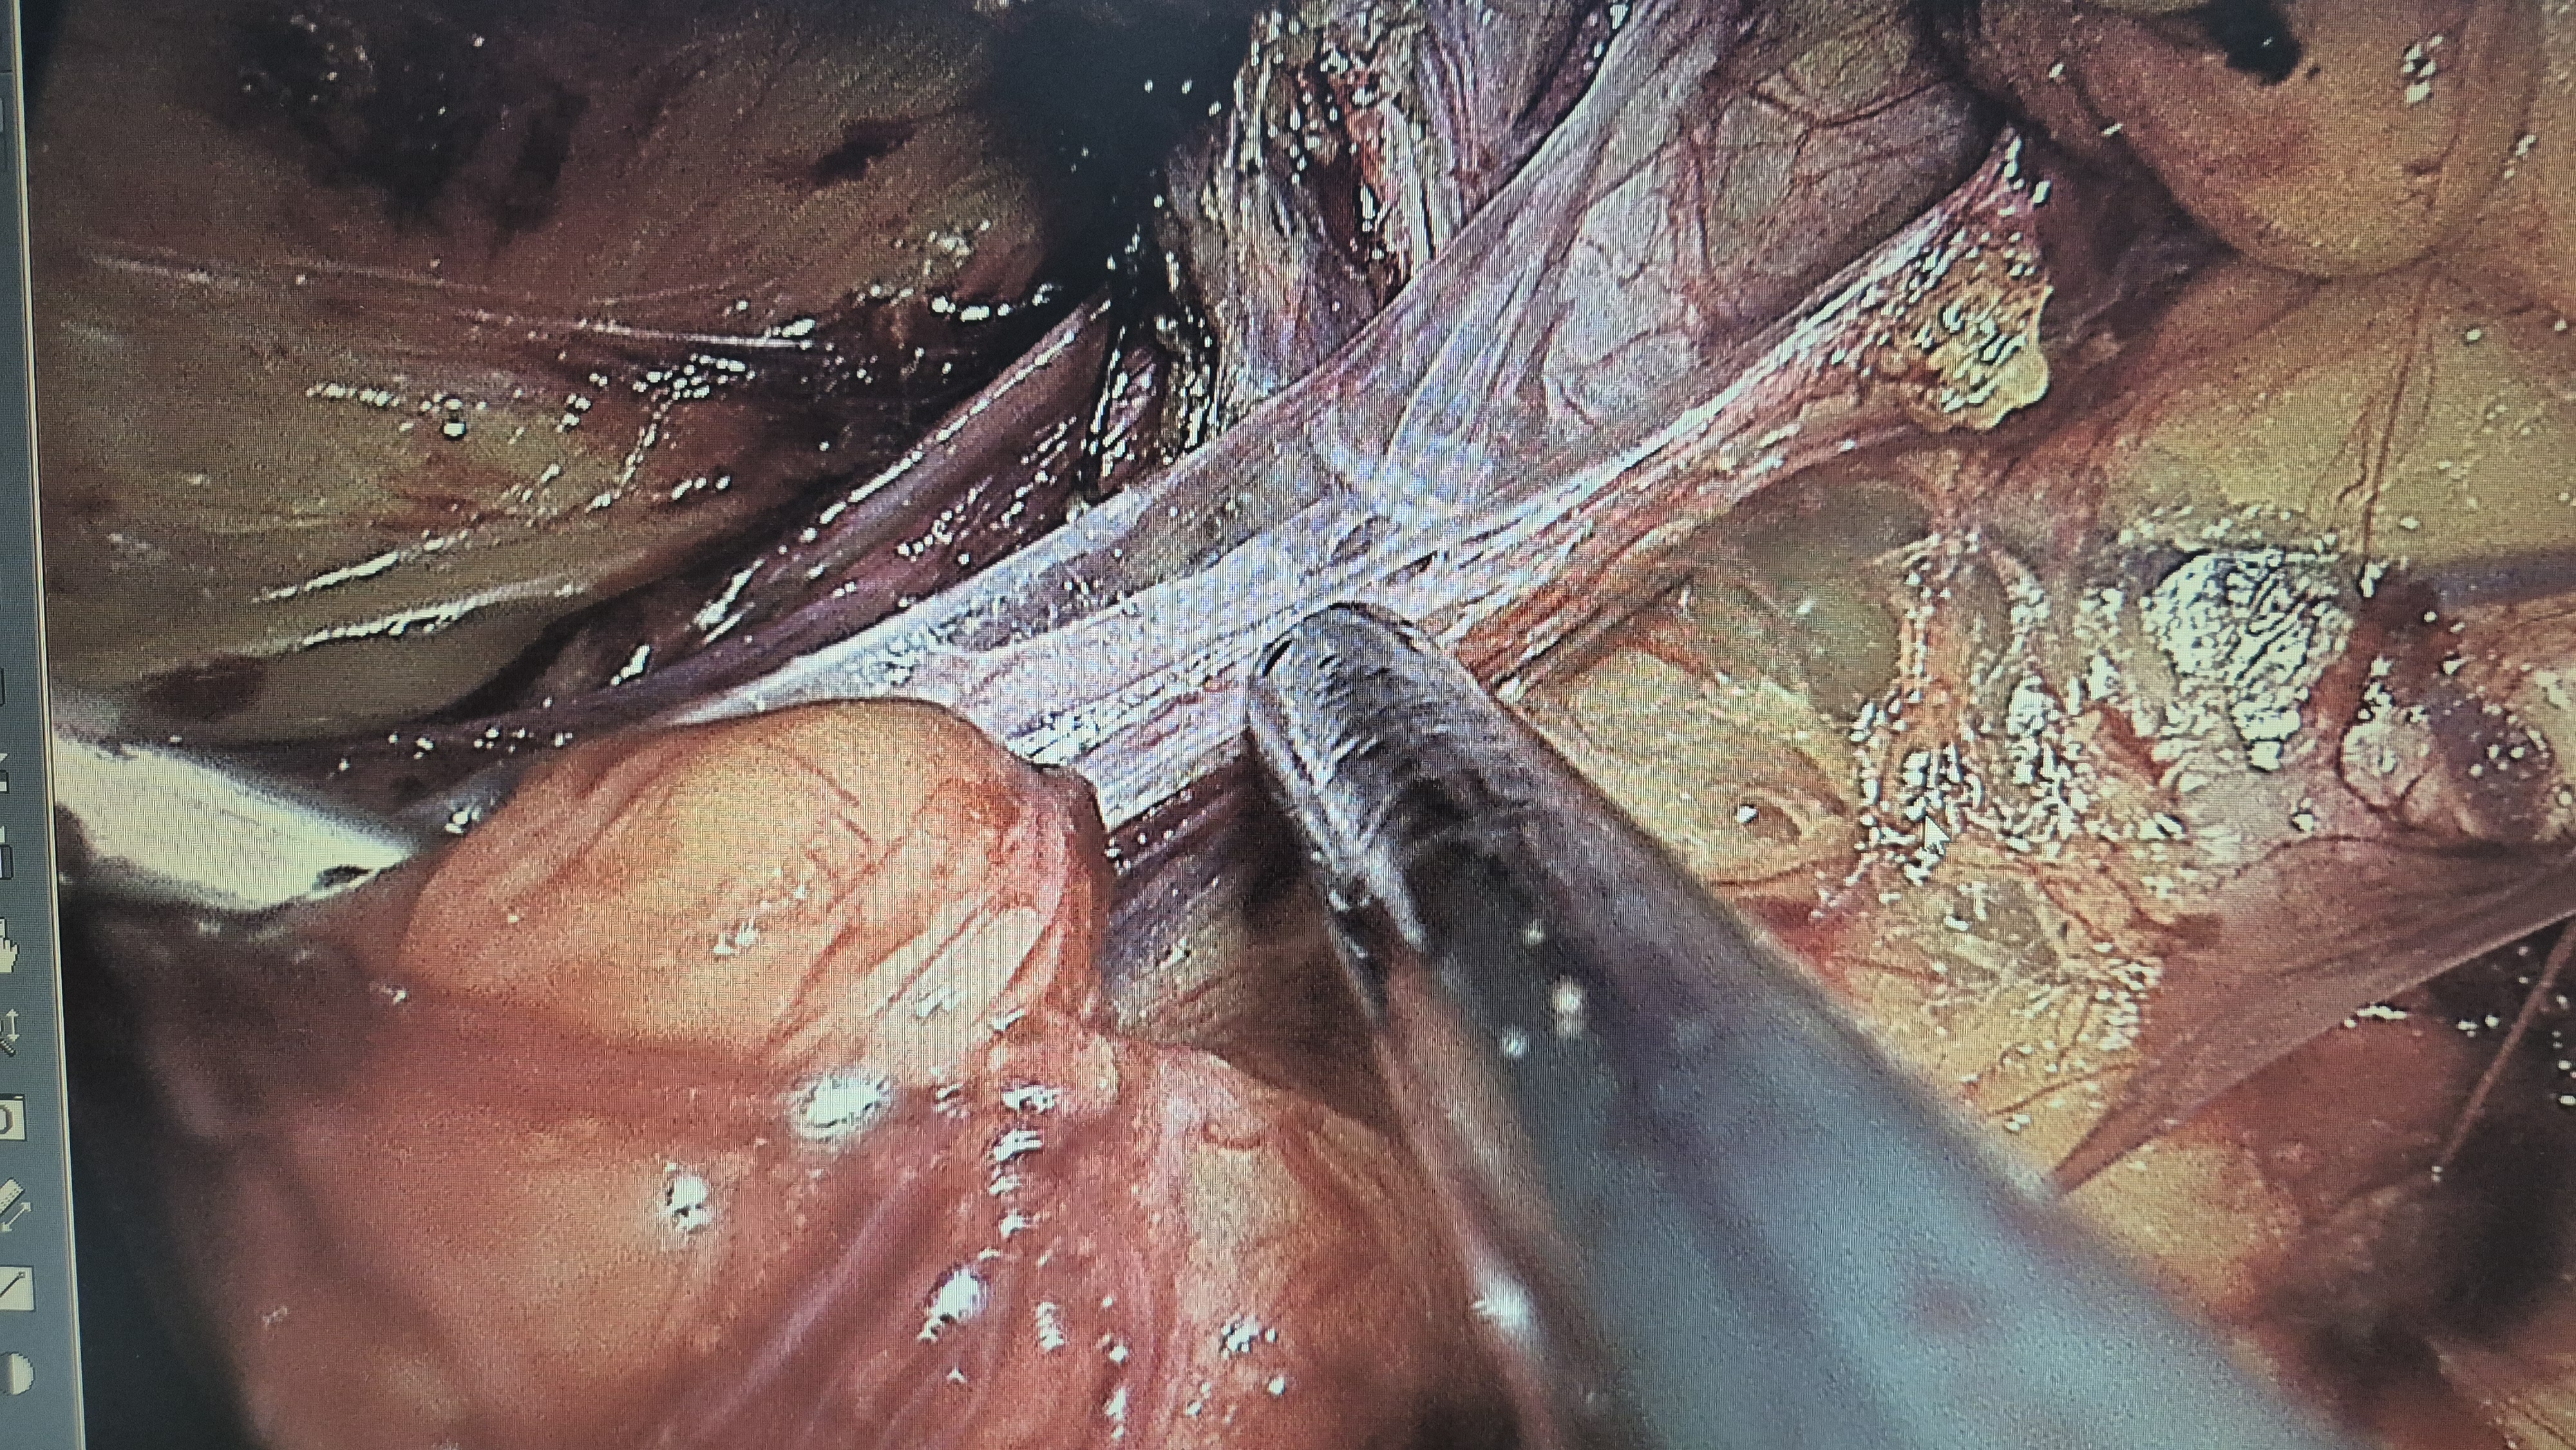

복강경 탈장교정술을 시행했습니다.

직접 서혜부 탈장 확인.

복원중.

복원후.

메쉬로 고정.